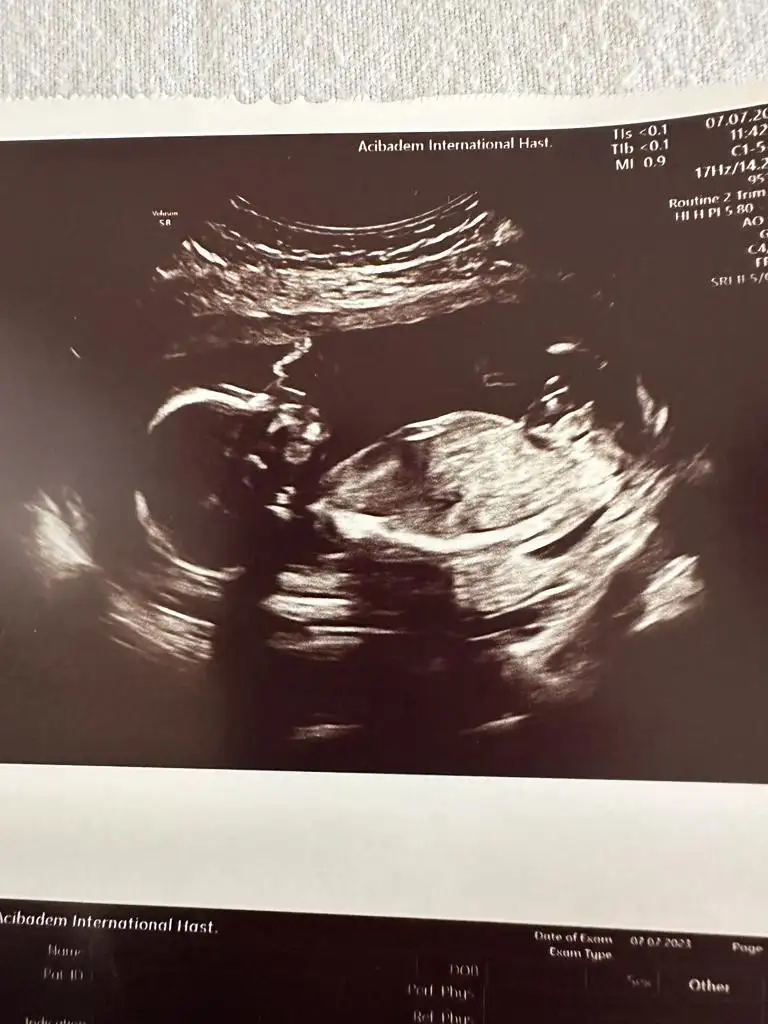

Yolunda canım, bazen yetişemiyorum konulara kaçırıyorum hep. Bugün detaylı ultrasonumuz vardı. Eşek sıpası yüzünü göstermedi biraz üzüldümSen de hiç görünmüyorsun. Yolunda dimi her şey

Yolunda canım, bazen yetişemiyorum konulara kaçırıyorum hep. Bugün detaylı ultrasonumuz vardı. Eşek sıpası yüzünü göstermedi biraz üzüldümçok şükğr sağlığımız yerinde

Benimki 1 saati geçti. Doktora ve bebeğin pozisyonuna göre değişiyor.Kizlar ayrintili ultrason kac dakika surdu yaptiranlar bana bilgi verebilirmi?

Benim 45 dk sürdü canımKizlar ayrintili ultrason kac dakika surdu yaptiranlar bana bilgi verebilirmi?